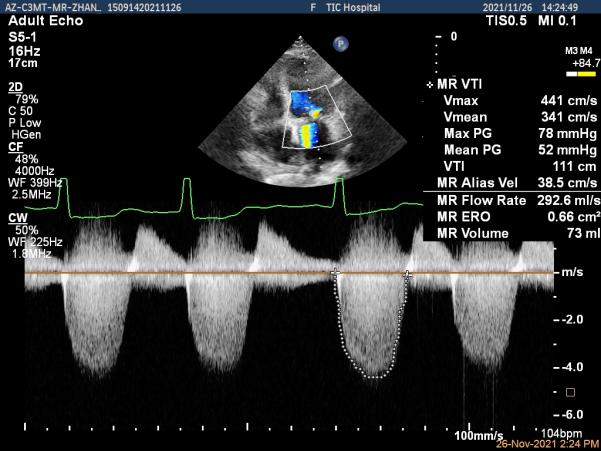

1.经胸超声心动图评估发现二尖瓣瓣叶增厚,瓣口面积小,提示有风湿性二尖瓣基础病变;

2. 患者P2区脱垂,这是导致患者二尖瓣大量反流最主要的原因;

3. 患者双房扩大,二尖瓣瓣环扩张,腱索牵拉后叶,瓣叶“扁平化“改变加重对合不良,因此房性FMR也参与了患者血流动力学改变的进程。

患者高龄、心衰时间较长、体型瘦小虚弱,无法耐受外科手术治疗,在门诊和入院初期评估时,由风湿性+功能性+退行性等多种原因导致的二尖瓣病变病理生理机制也给经导管介入治疗带来极大的挑战。门诊经胸超声心动图提示风湿性改变伴有轻度二尖瓣狭窄是传统意义上经导管缘对缘修复技术的禁忌,脱垂区后叶因AFMR参与被牵拉较短也是TEER的技术瓶颈。但患者反复心衰发作,病情恶化迅速,积极治疗重度的二尖瓣反流将是改善患者预后的一线生机。因此入院后我们通过经食道超声给这位患者进行了细致的评估后发现,患者的确有二尖瓣瓣叶增厚的改变,跨瓣压差在3-5mmHg,二尖瓣瓣口面积在4.43cm²,并没有明显的开放受限,瓣膜面积相对来说是TEER治疗的临界水平,后叶长度约7mm,尽管相对较短,在我们前期的TEER治疗患者中也可以达到充分的钳夹长度。因此经过心脏团队反复的综合评估,认为该患者有TEER治疗成功的机会,在充分药物治疗,患者心衰症状改善且病情平稳后,在患者以及家属强烈要求下,我们积极完善术前准备,择期行TEER治疗。

术前超声评估结果

术前超声诊断

Qlab软件勾画估测瓣口面积约:4.42cm²

二尖瓣口平均跨瓣压差:5mmHg